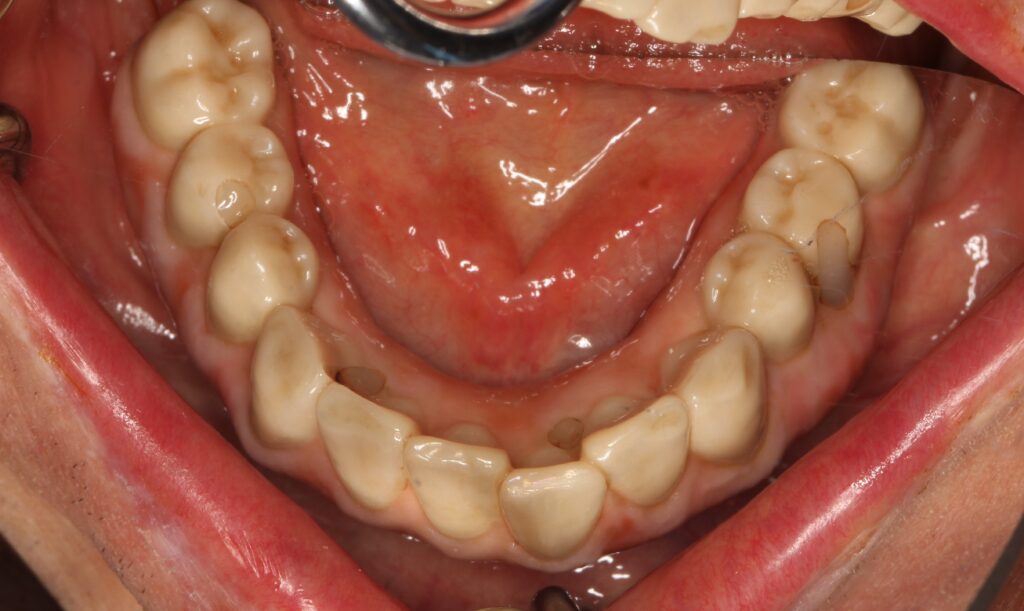

A selection of full arch fixed implant bridge patients after 5 years of wear